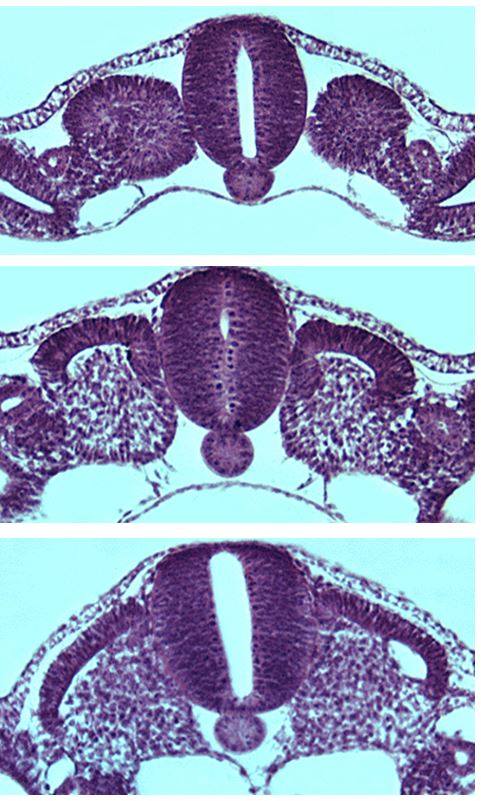

somieten transversaal

Somite_001

somitogenesis